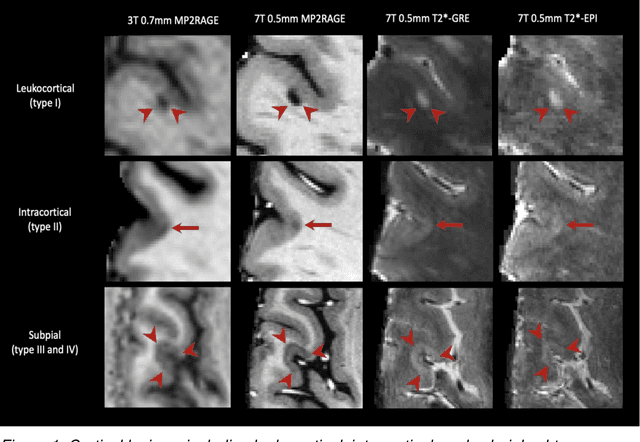

Abstract:The current multiple sclerosis (MS) diagnostic criteria lack specificity, and this may lead to misdiagnosis, which remains an issue in present-day clinical practice. In addition, conventional biomarkers only moderately correlate with MS disease progression. Recently, advanced MS lesional imaging biomarkers such as cortical lesions (CL), the central vein sign (CVS), and paramagnetic rim lesions (PRL), visible in specialized magnetic resonance imaging (MRI) sequences, have shown higher specificity in differential diagnosis. Moreover, studies have shown that CL and PRL are potential prognostic biomarkers, the former correlating with cognitive impairments and the latter with early disability progression. As machine learning-based methods have achieved extraordinary performance in the assessment of conventional imaging biomarkers, such as white matter lesion segmentation, several automated or semi-automated methods have been proposed for CL, CVS, and PRL as well. In the present review, we first introduce these advanced MS imaging biomarkers and their imaging methods. Subsequently, we describe the corresponding machine learning-based methods that were used to tackle these clinical questions, putting them into context with respect to the challenges they are still facing, including non-standardized MRI protocols, limited datasets, and moderate inter-rater variability. We conclude by presenting the current limitations that prevent their broader deployment and suggesting future research directions.

Abstract:The automated detection of cortical lesions (CLs) in patients with multiple sclerosis (MS) is a challenging task that, despite its clinical relevance, has received very little attention. Accurate detection of the small and scarce lesions requires specialized sequences and high or ultra-high field MRI. For supervised training based on multimodal structural MRI at 7T, two experts generated ground truth segmentation masks of 60 patients with 2014 CLs. We implemented a simplified 3D U-Net with three resolution levels (3D U-Net-). By increasing the complexity of the task (adding brain tissue segmentation), while randomly dropping input channels during training, we improved the performance compared to the baseline. Considering a minimum lesion size of 0.75 {\mu}L, we achieved a lesion-wise cortical lesion detection rate of 67% and a false positive rate of 42%. However, 393 (24%) of the lesions reported as false positives were post-hoc confirmed as potential or definite lesions by an expert. This indicates the potential of the proposed method to support experts in the tedious process of CL manual segmentation.